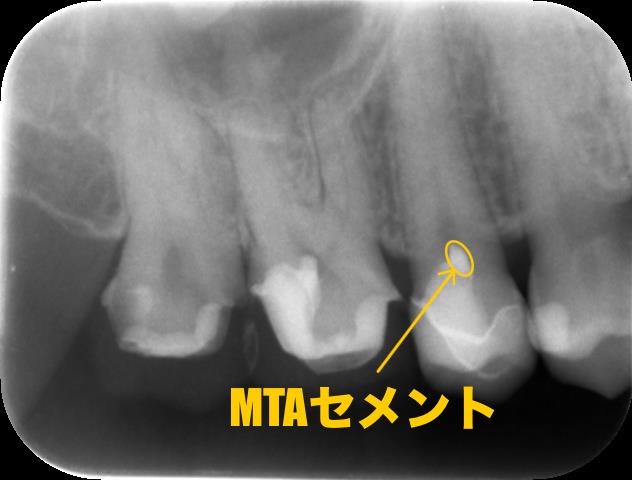

こちらが術後のレントゲン写真です

この補綴はオンレーといって鍋の蓋のような構造をしています。噛む面を全て覆っているため被せ物に近い強度が得られます。また、被せ物に比べて歯の切削量が少なく済むため、当院では多く用いられています。